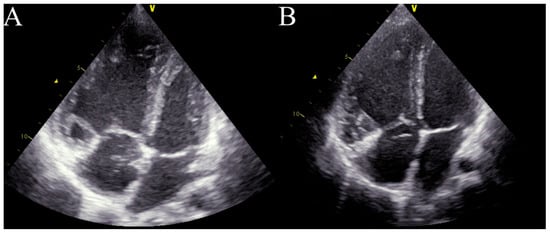

Echocardiography (Figure 1) showed dilatation of the pulmonary artery ((PA) − 28 mm, z-score + 3.34), a diameter of the right ventricle in the upper limit of normal ((RV) diameter − 2.4 mm, z-score + 1.11), with high-velocity tricuspid regurgitation (4.3 m/s) and an elevated estimated RV systolic pressure ((RVSP) − 85 mmHg) and estimated mean pulmonary arterial pressure ((mPAP) − 59 mmHg). Right heart catheterisation confirmed precapillary pulmonary hypertension, with an mPAP of 49 mmHg, pulmonary artery wedge pressure (PAWP) of 12 mmHg, pulmonary vascular resistance of 12.2 Wood units (Wu), and a cardiac index of 3.45 L/min*m2, assessed by means of a thermodilution method. The acute vasoreactivity test with nitric oxide (dosage 20 ppm) was negative. The differential diagnosis to search for clear causes of pulmonary hypertension was performed according to the current guidelines [1]. The patient did not have any exposure to toxins or medications. AngioCT excluded a thromboembolic origin, and full rheumatological and infectious disease panels were performed, as well as molecular analysis. No pathological mutation was confirmed. A diagnosis of IPAH was made, and the patient qualified for combined PAH-targeted therapy. Full doses of bosentan (31.25 mg twice daily) and sildenafil (20 mg thrice daily) were administered, with no side effects. The patient’s condition stabilized for 3 months.

Figure 1. Initial echocardiography.